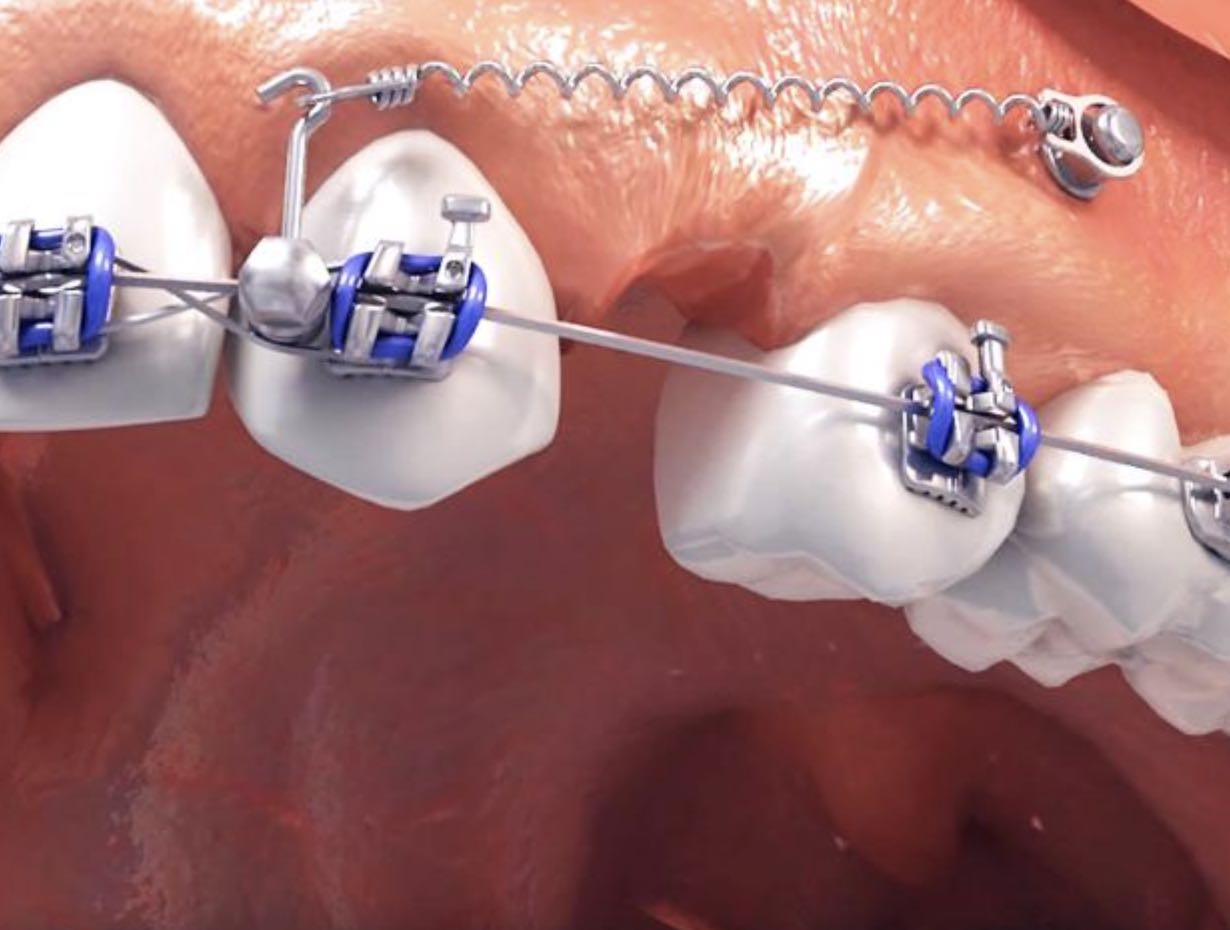

Лечение при помощи брекет-системы позволяет врачу использовать возможности не только дуги, но также микроимплантов. Их можно устанавливать и независимо от брекетов, например, на этапе подготовки для расширения верхней челюсти.